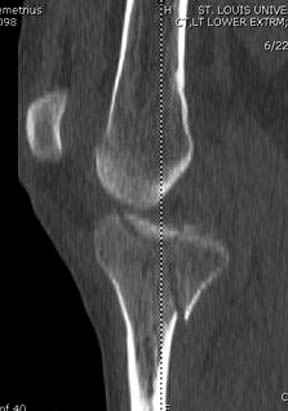

Здесь как раз тот случай, когда результат зависит не только от мастерства хирурга, но и от наличия современных методов исследования. Например, КТ которая поможет рассчитать направления шурупов и установку импланта. Кроме этого, поможет определиться с доступом.

На представленных предоперационных срезах КТ огромный задне-медиальный фрагмент расположен больше кзади, чем медиально. Для планирования, кроме поперечных срезов, надо ориентироваться на корональные срезы, которые укажут топографию верхушки медиального фрагмента.

Надеюсь, представленные снимки разных случаев помогут разобраться в тактике, и критика примется без личной обиды.